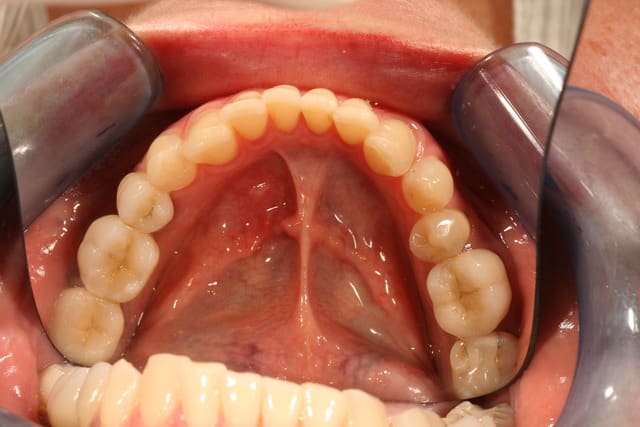

elle a eu gouttière en relation centrée un moment, puis avec l'amélioration des symptomes, (j'ai juste amélioré son calage je pense) on est passé au fixe, avec augmentation de la DV. Il y a eu implants 25 26 après sinus lift, couronne 36, bridge 45/47, onlay 16 et facettes palatines en composite de 13 à 23 et composites sur les incisives en bas

j'ai refait les compos des incisives avant de lancer tout ça, pour être sur du collage, et on aussi fait un éclaircissement.

pour les points de caries que j'ai découverts entre 22 et 23, j'ai essayé d'en enlever un maximum en préparant, mais c'est vrai qu'en regardant les photos ça semble un peu limite sur la 22, peut être que j'y repasserait un coup de fraise avant de coller les facettes.

il est aussi prévu une gouttière pour la nuit pour protéger tout ça juste après avoir collé les facettes

Je suis assez d'accord pour la préparation supragingivale dans certains cas , être le moins invasif est l'axiome à retenir , inutile de s'enfoncer éperdument au risque de blesser le sulcus et l'attache .

Encore faut-il calculer son coup question teinte , et bien garder la même , l'application se fait alors pour des cas esthétiques de changement de forme des dents uniquement .

je ne comprend pas l'utilité du fil pour des préparations supra gingivales de1/2mm

je n'ai rentré le fil qu'aux endroits ou j'étais juxta ou très peu supra

quand à savoir pourquoi je suis juxta à certains endroits et supra à d'autres, je dois avouer que je sais pas trop, j'ai du me dire qu'il fallait descendre un peu en interdentaire parce que les dents étaient assez écartées et que ça permettrait au prothésiste de me faire un plus joli profil d'emergence à ces endroits.

je préfère le fil dans les cas avec plusieurs préparations dans ce style, parce qu'on peut mettre un seul fil et tout tirer d'un coup en injectant derrière

la plupart du temps je fais à l'expasyl, mais c'est trop long à rincer quand il y a trop de dents, travaillant seul le matériau à empreinte commence à prendre le temps de tout rincer

j'aurais peut être pu me passer complètement de retraction gingivale dans ce cas, mais ça me donnera une raison de râler sur mon prothésiste qui m'aura bouffé les profil d'émergence au détourage